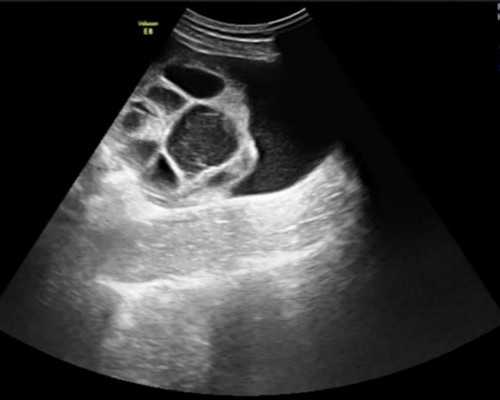

单角子宫是一种比较罕见的妇科疾病,患者的子宫只有一个角度,而非正常的两个角度。这种情况会给女性生育带来困难,但是近年来试管婴儿技术的发展,为单角子宫患者带来了新的希望。那么单角子宫做试管婴儿成功率真的高吗?试管婴儿技术对于治疗单角子宫具有明显优势。由于单角子宫造成了受孕困难,许多患者往往采取传统的手术方法进行治疗。然而这种方法不仅效果不佳,还存在许多风险和并发症。相比之下,试管婴儿技术可以更好地克服这些问题,并提高受孕成功率。

在试管婴儿过程中,医生会通过辅助生殖技术将女性排卵出的卵子与男性精液体外结合,在实验室中培养出胚胎后再将其移植入女性子宫内部。对于单角子宫患者而言,在胚胎移植过程中,医生可以更加精确地选择适合的位置进行移植,以增加受孕的成功率。